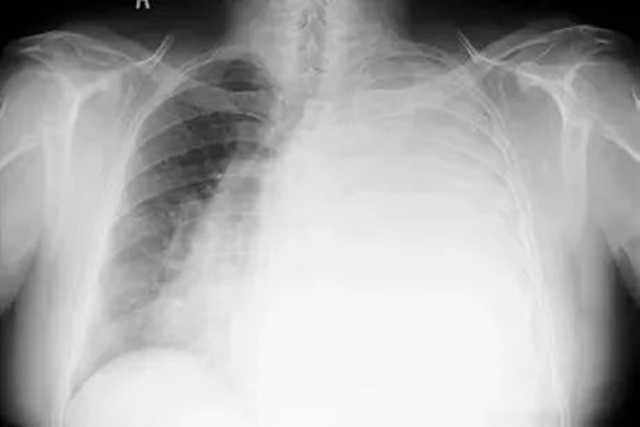

“白肺”一般是指重症肺炎在X光检查下的表现,其肺部呈现一大片的白色状态,白肺形成一般都预示着肺部被炎症所广泛浸润。

白肺

正常健康的肺,在X光和CT上都是透光的,并且显示为“黑色”。但如果肺部有严重的疾病(如肺炎或者肺部肿瘤),或者有大量的胸腔积液,让健康的肺组织不再具有正常的通气和其他交换功能,肺泡组织被破坏了,这时候在X光和CT上就表现为“白色”。